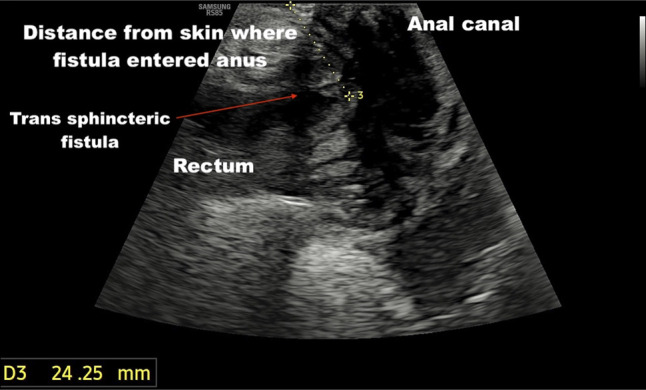

Abstract Image